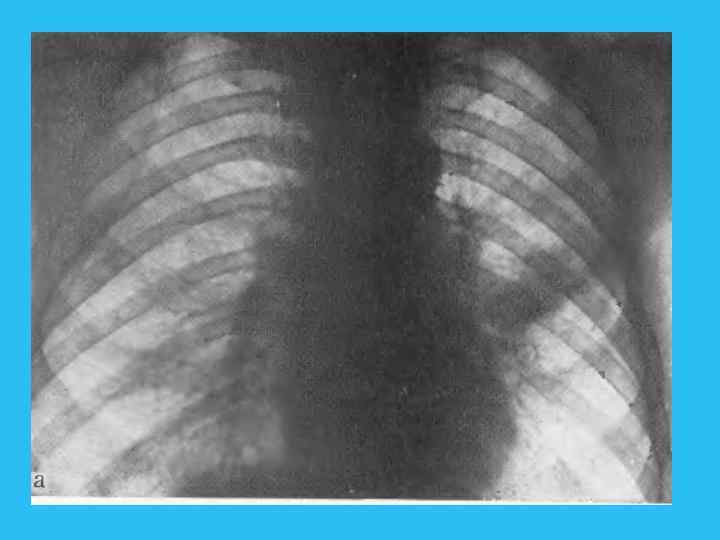

Четвертая фаза соответствует выраженной клинической и достаточно демонстративной рентгенологической картине заболевания. В этот период отчетливо виден опухолевый узел, иногда достигающий нескольких санти метров в диаметре. Связь узла с бронхом и прогрессирующий рост в сто рону последнего приводит к сужению просвета II степени и развитию обтурационной эмфиземы. Нередко при сравнительно быстром метастазировании опухоли в лимфа тические узлы видимая тень в легком представляет собой отображение первичного опухолевого узла, слившегося с метастатически измененными увеличенными лимфатическим узлами (рис. 244). При этом опухолевый узел в корневой зоне часто приобретает полициклические контуры. Обна ружение увеличенных трахеобронхиальных и паратрахеальных лимфати ческих узлов иногда приводит к неправильной расшифровке видимой кар тины, когда все изменения связываются с системным поражением лимфа тических узлов легкого и средостения. По мере развития болезни растет первичный опухолевый узел и стадия гиповентиляции, а затем клапанного вздутия, сменяющаяся ателектазом. Развитие ателектаза может привести к потере изображения опухолевого узла на фоне спавшегося сегмента или зоны. Возникновение ателектаза, так же как и при эпдобронхиальной опухоли, способствует развитию ряда осложнении, о которых уже говорилось. Наступает пятая фаза течения опухолевого процесса. При переходе от экспансивной к инфильтративной фазе роста опухоль начинает распространяться по ходу бронхов и сосудов, что находит своеотражение на рентгенограммах. При этом узел теряет свои четкие очерта ния, появляются грубые тяжистые тени, расходящиеся от опухолевого узла в легочную ткань (рис. 245).

Рис. 245. Ателектаз язычка. Узел в корневой зоне отчетливо не виден. а — прямая рентгенограмма; б — бокивая томограмма; опухолевый узел в корневой зоне отчетливо не виден; в — томограмма. Позиция PS (45°). Опухолевый узел обрастает все разветвления верхне долевого, язычновогои промежуточного бронхов.